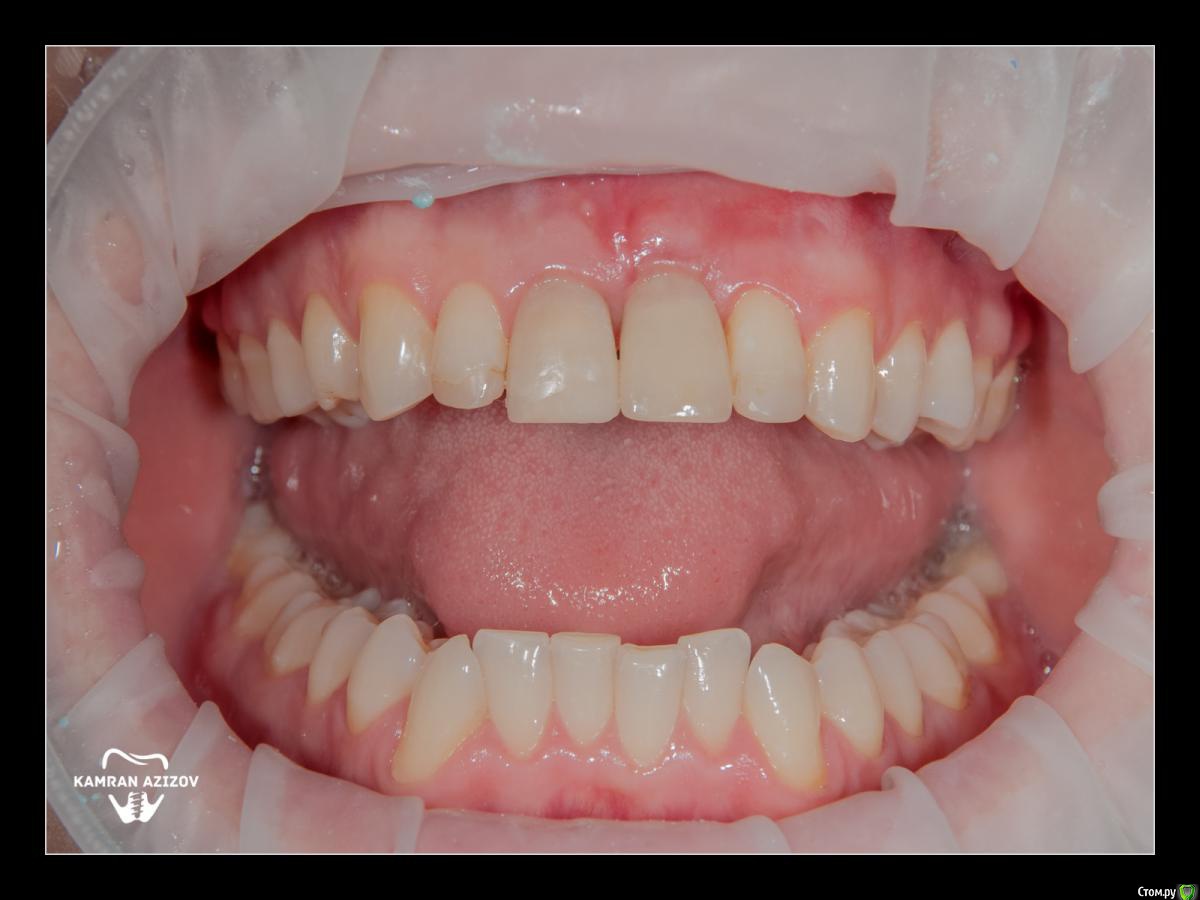

kamranchick Опубликовано 8 октября, 2019 Поделиться Опубликовано 8 октября, 2019 удаление зуба+консервация лунки с вестибулярным ССТчерез 2 месяца имплантация с фдм по карлоссучерез 4 месяца замена на более длинный фдм и широкийпостоянная коронка 5 Ссылка на комментарий